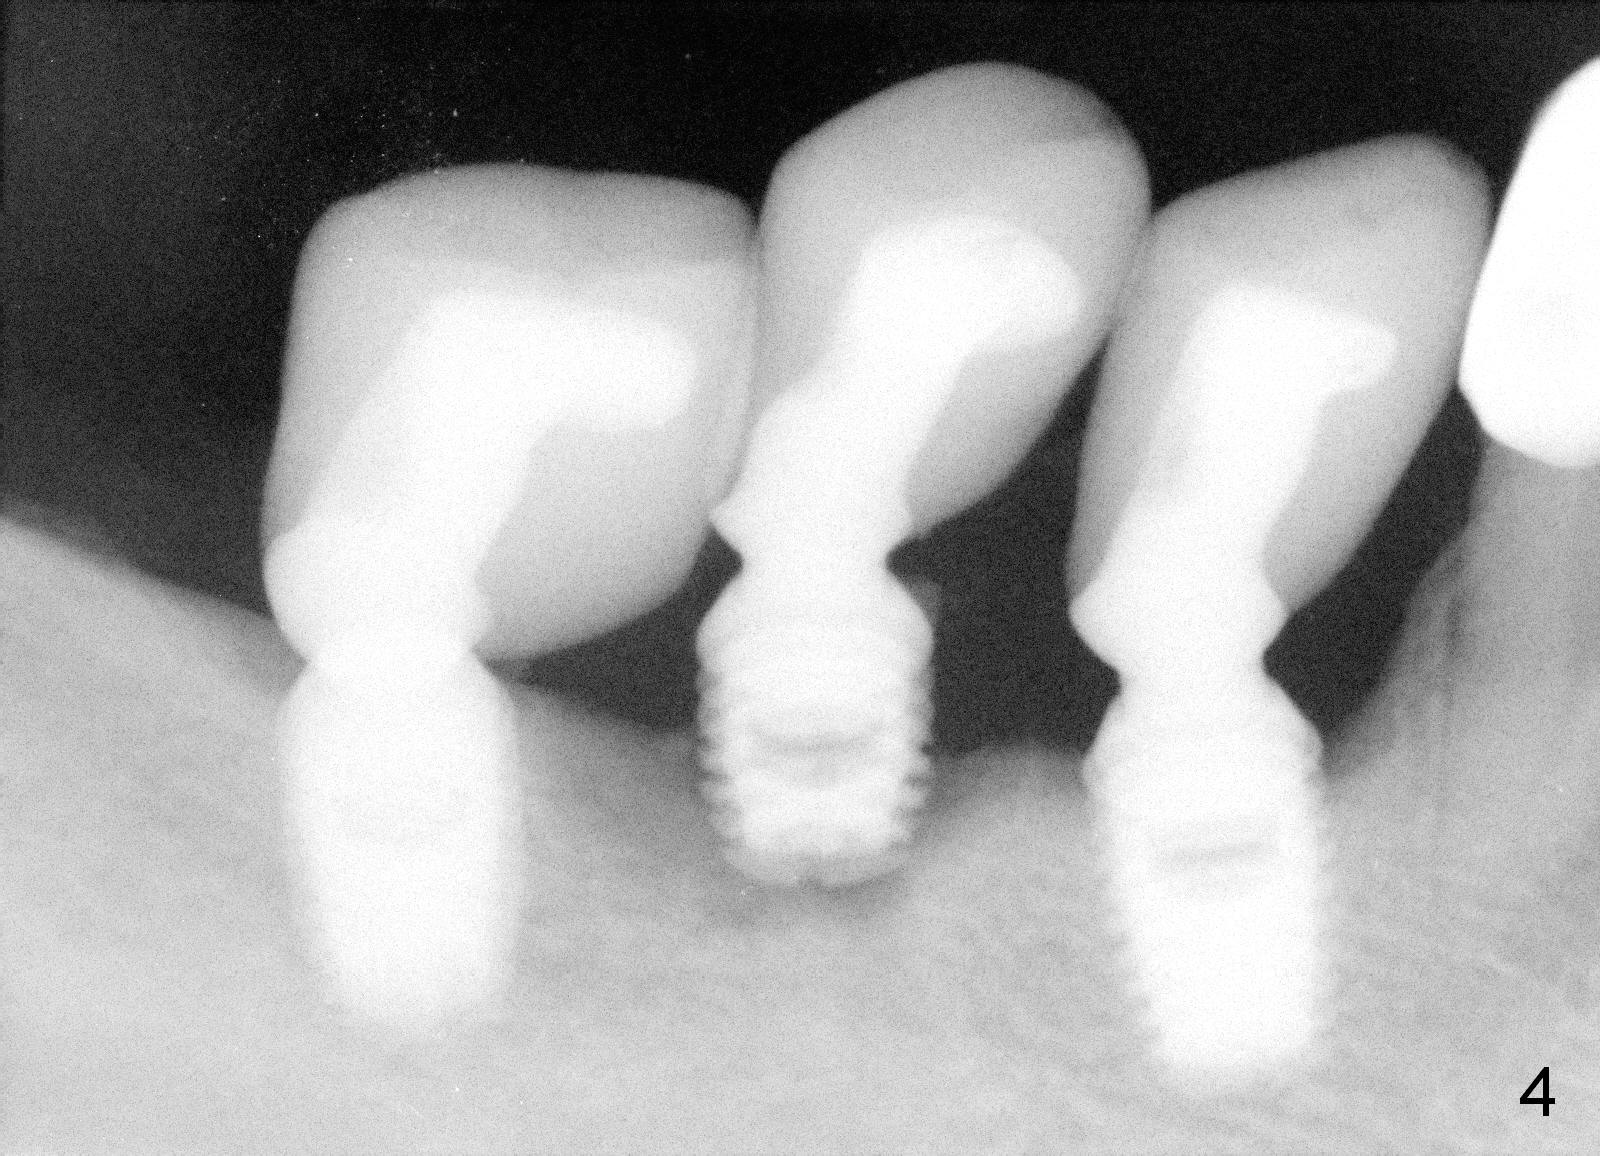

A 48-year-old man had 3 implants placed at #28-30 nearly 10 years ago (Fig.1). The implant at #29 is 4.5x6 mm because of proximity to the Mental Foramen. Bone shows gradual resorption around the implant at #29 two and 5 years postop (Fig. 2,3 >). It became loose when he accidentally bit on a piece of bone (Fig.4). A 4.5x11 (Fig.4) or 14 (Fig.2) mm tissue-level implant will be placed after Metronidazole treatment. CT will be taken tomorrow before surgery to further confirm the bone height. Since the previous implant was placed distally, the new one should be placed more mesially.